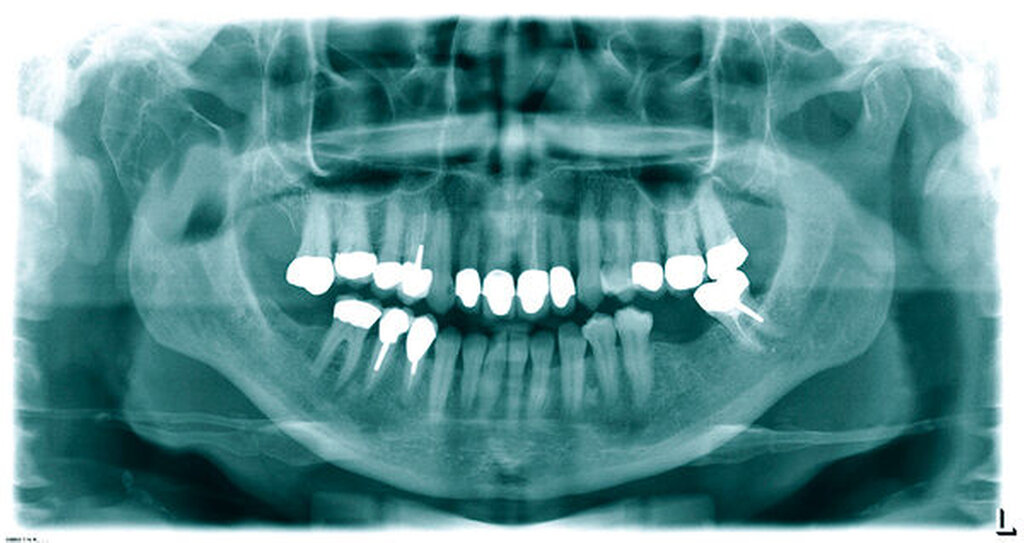

Im Jahr 2014 konsultierte uns die Patientin erneut und berichtete über eine progrediente Hypästhesie und Parästhesie des rechten N. alveolaris inferior. Die klinische Untersuchung zeigte eine harte und schmerzhafte Schwellung im Bereich rechten Kiefergelenks. Die Mundöffnung war auf 30 Millimeter reduziert. Die Orthopantomografie und der CT-Scan zeigten eine multizystische Auftreibung des rechten Ramus ascendens mandibulae sowie des rechten Capitulums mandibulae, die zu einer ausgeprägten Deformation führte (Abbildungen 1 und 2).

Das charakteristische röntgenologische Erscheinungsbild des Tumors wird als uni- oder multilokuläre radiologische Aufhellung beschrieben, die Seifenblasen oder Honigwaben ähnelt. Radiologisch kann sie sowohl gut abgrenzbar als auch unscharf begrenzt sein [Kawai et al., 1997; Peltola et al., 1994].

Die Darstellung einer multilokulären radioluzenten Läsion im rechten Ramus ascendens und Kondylus, einschließlich des Kiefergelenks mit starker Deformation und seifenblasenähnlicher Erscheinung mit klar definierten Rändern, passt zu den in der Literatur für das odontogene Myxom beschriebenen radiologischen Merkmalen [Kawai et al., 1997]. Die histopathologische Analyse des Präparats durch das Institut für Pathologie des Universitätsspitals Basel in der Schweiz (Prof. Dr. Jundt) zeigte stern- und spindelförmige Zellen innerhalb einer myxoiden Matrix, die als typische histologische Merkmale für das odontogene Myxom gelten.